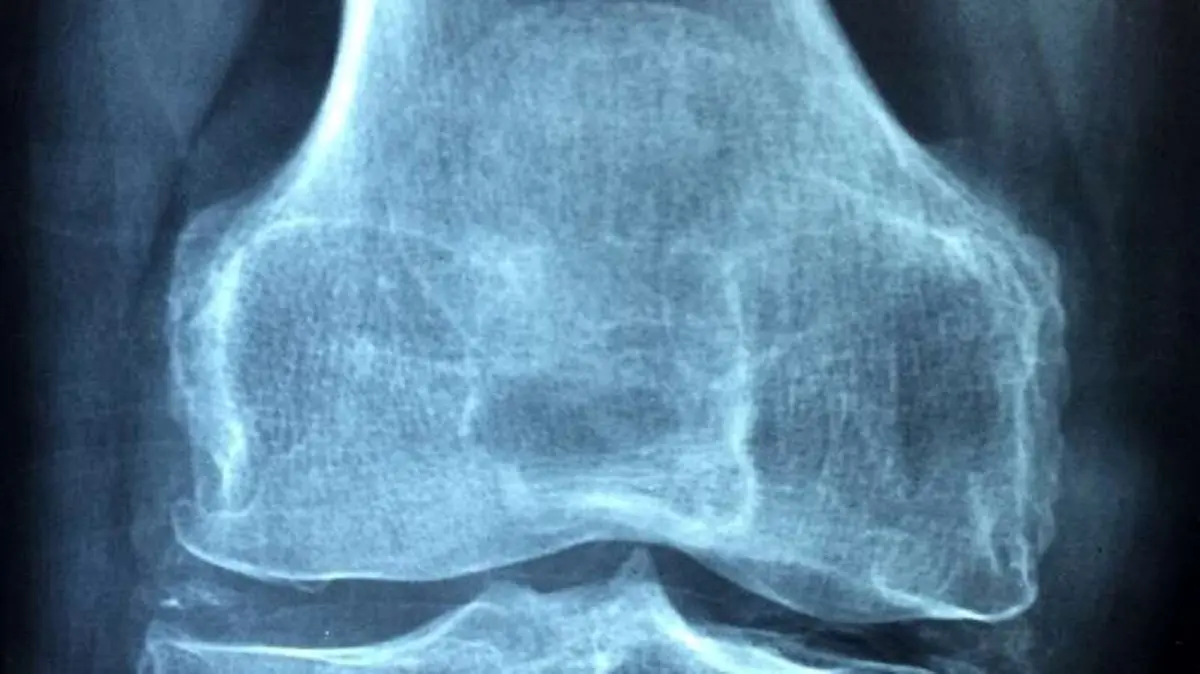

رماتیسم مفصلی زمانی رخ میدهد که سیستم ایمنی بدن به بافت سالم حمله و آن را مورد تجزیه قرار میدهد. در بیماری رماتیسم مفصلی، پوشش مفاصل دست، زانو و مچ مورد حمله قرار میگیرد. علیرغم شیوع این بیماری، هیچ درمان قطعی برای آن وجود ندارد و محققان به دنبال روشهای موثر درمان هستند.